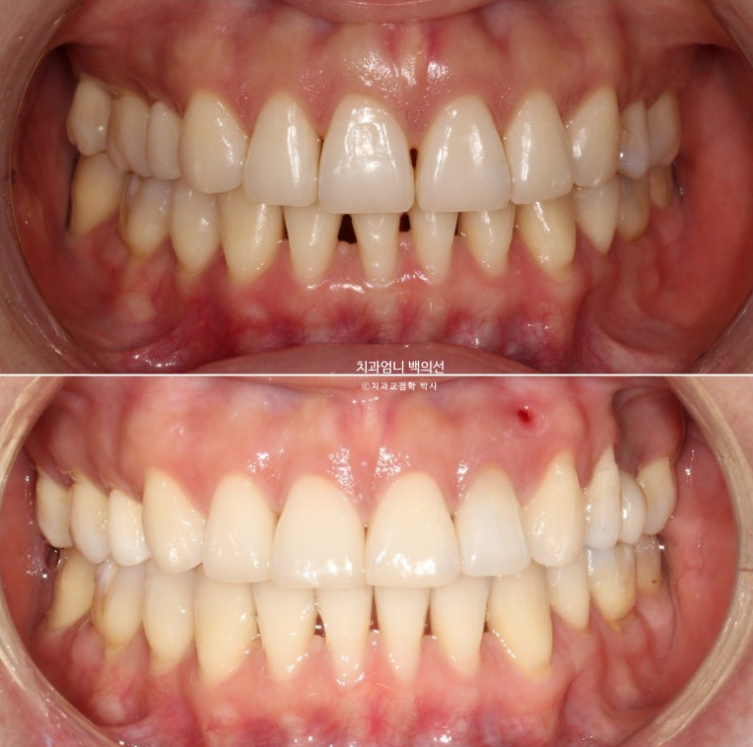

23.08~25.06

23년 8월 재교정치료를 위해 내원한 환자분입니다.

환자분은 어금니가 닿도록 끝까지 물면 아래턱이 뒤로 밀리는 증상때문에 재교정을 원했습니다.

또한 아래턱이 뒤로 밀리다보니 아래 앞니가 뒤로 너무 쑥 들어가보이는 부분도 개선을 원하셨습니다.

하지만 이 경우는 옥니나 입매 등 단순 미적목적으로 역교정이 필요한 경우와는 다릅니다.

이전 교정에서 윗니의 무리한 후방이동으로 아래턱이 뒤로 밀리는 증상이 뚜렷하여 안모를 심하게 해칠뿐 아니라 턱관절에 무리가 오는 경우라 역교정을 해서라도 턱의 위치를 개선하는 것이 좋습니다.

위 앞니 중심선을 회복하고 치아 갯수의 밸런스 및 교합을 개선하기 위해 결손된 큰어금니 1개는 교정으로 공간을 다시 벌려 임플란트를 하기로 합니다.

윗니 중심선이 코와 인중 및 얼굴과 맞아진 것은 치료시작 1년 후 입니다.

이때부터 아래 치아에도 클리피씨 장치를 붙이고 배열을 시작했습니다.

치료시작 1년 3개월차, 결손된 큰어금니 공간이 충분히 확보되어 드디어 임플란트를 식립했습니다.

교합 안정화 및 마무리과정을 거쳐 25년 6월 드디어 재교정 치료를 마무리 했습니다.

총 치료기간은 1년 10개월입니다.

이제 앞니 중심선은 코와 인중과 정확히 맞습니다.

2급이었던 양측 어금니 교합관계는 비로소 1급이 되었습니다.

덕분에 중심선도 개선하고 어금니 교합관계도 1급이 되었으며 앞니가 뒤로 쓰러진 옥니도 고칠 수 있었습니다.

소량의 치간삭제로 기존의 블랙트라이앵글 사이즈를 줄였습니다.